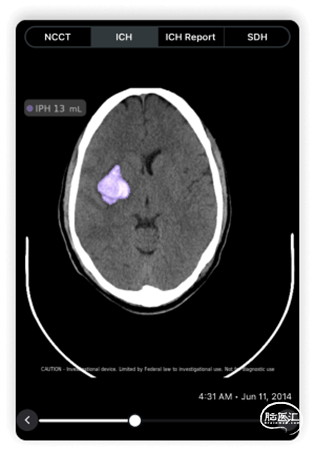

Viz.ai旗下的Viz ICH Plus旨在自动识别、标记和量化非对比CT分割脑区的出血量,用于分析颅内高密度影、侧脑室和中线移位,并提供脑出血量的测量数据,放射科、神经外科等医生可将Viz ICH Plus无缝整合至工作流程当中。(推荐阅读:《【风向标】Viz ICH Plus获FDA 510(k)批准,用于颅内出血检测和治疗协调》)